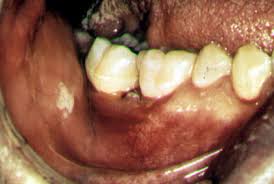

Figura 3. Lesión cutánea en la baca con histoplasmosis.

La histoplasmosis es una infección micótica de amplia diseminación que se

presenta a nivel mundial. En los Estados Unidos esta infección es más común

en los estados del sudeste, de la zona atlántica media y en los estados

centrales.

Los pulmones son el portal de entrada para esta infección. El histoplasma

crece como un moho en el suelo y la infección es ocasionada por la

inhalación de partículas micóticas transportadas por el aire. El suelo

contaminado con los excrementos de aves o de murciélagos puede tener

mayores concentraciones de moho.

El hongo produce esporas que se mesclan con el aire al disturbar el suelo

contaminado. El respirar las esporas es la causa de la infección. Usted no

puede contraer la histoplasmosis de otra persona.

La histoplasmosis puede ser asintomática; es posible que se presente un

corto período de infección activa o que ésta se disemine por todo el

cuerpo. La mayoría de los pacientes con histoplasmosis sintomática

desarrollan un síndrome similar al de la influenza y enfermedades

pulmonares relacionadas con una neumonía subyacente o con otro compromiso

pulmonar. Las personas con enfermedad pulmonar crónica, como el enfisema o

la bronquiectasia, pueden tener un riesgo mayor de ser atacados por una

presentación más severa de esta enfermedad.

Si el cuerpo responde a la infección con una inflamación extrema

(irritación e inflamación con presencia de células inmunes adicionales en

el área afectada), hasta el 10% de los pacientes puede sufrir

complicaciones inflamatorias que involucran la piel, los

huesos/articulaciones o el revestimiento del corazón (pericardio).

A menudo se le llama la "enfermedad de la cueva" pues se ve a

veces en personas que exploran cuevas como forma de recreación. Los murciélagos,

perros, gatos, ratas, zorrillos, zarigüeya, zorros y otros animales pueden

contraer la histoplasmosis y pueden desempeñar un papel en la trasmisión de

la enfermedad.